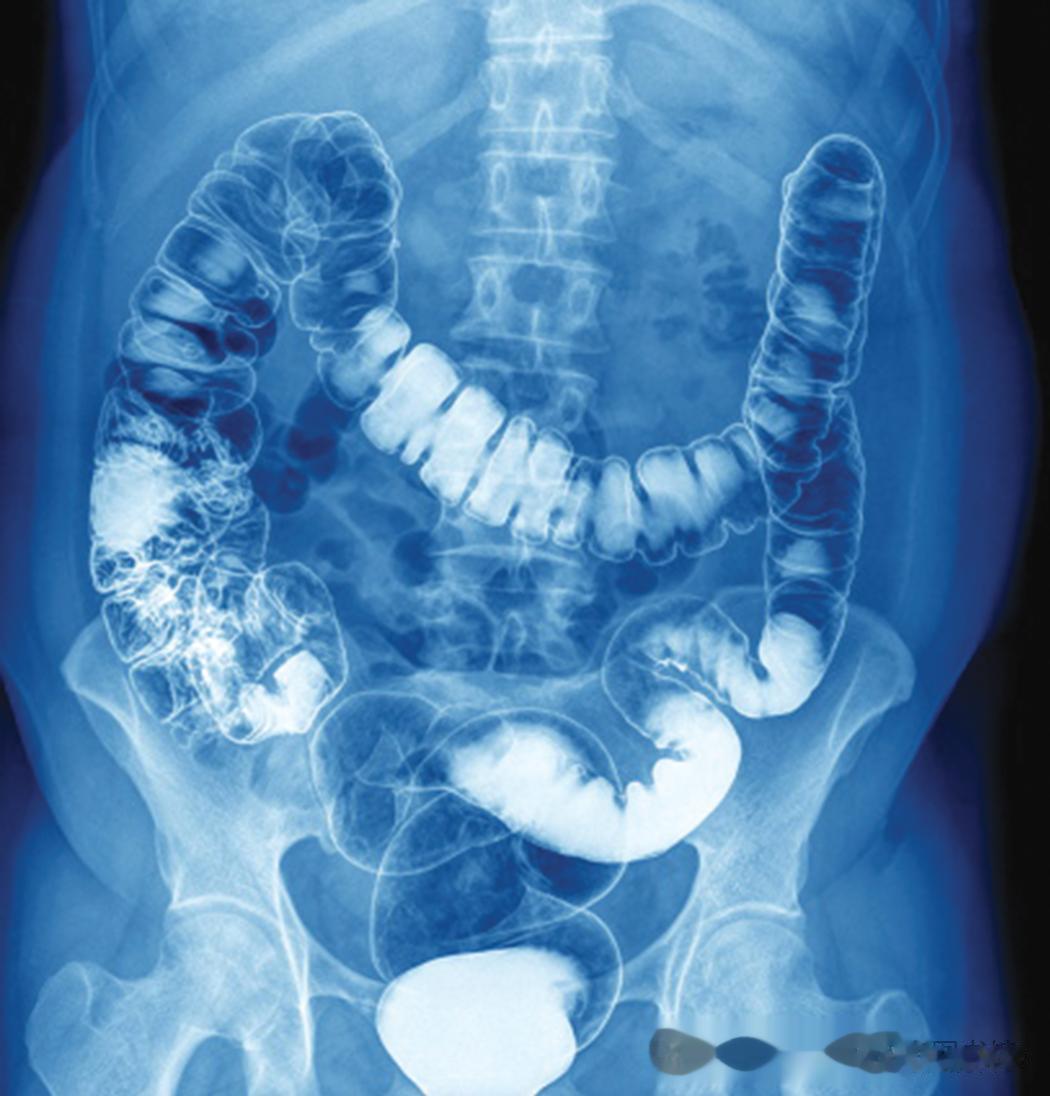

患者摄入的显影剂的大肠X线片